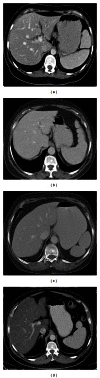

Spleen can have a wide range of anomalies including its shape, location, number, and size. Although most of these anomalies are congenital, there are also acquired types. Congenital anomalies affecting the shape of spleen are lobulations, notches, and clefts; the fusion and location anomalies of spleen are accessory spleen, splenopancreatic fusion, and wandering spleen; polysplenia can be associated with a syndrome. Splenosis and small spleen are acquired anomalies which are caused by trauma and sickle cell disease, respectively. These anomalies can be detected easily by using different imaging modalities including ultrasonography, computed tomography, magnetic resonance imaging, and also Tc-99m scintigraphy. In this pictorial essay, we review the imaging findings of these anomalies which can cause diagnostic pitfalls and be interpreted as pathologic processes.